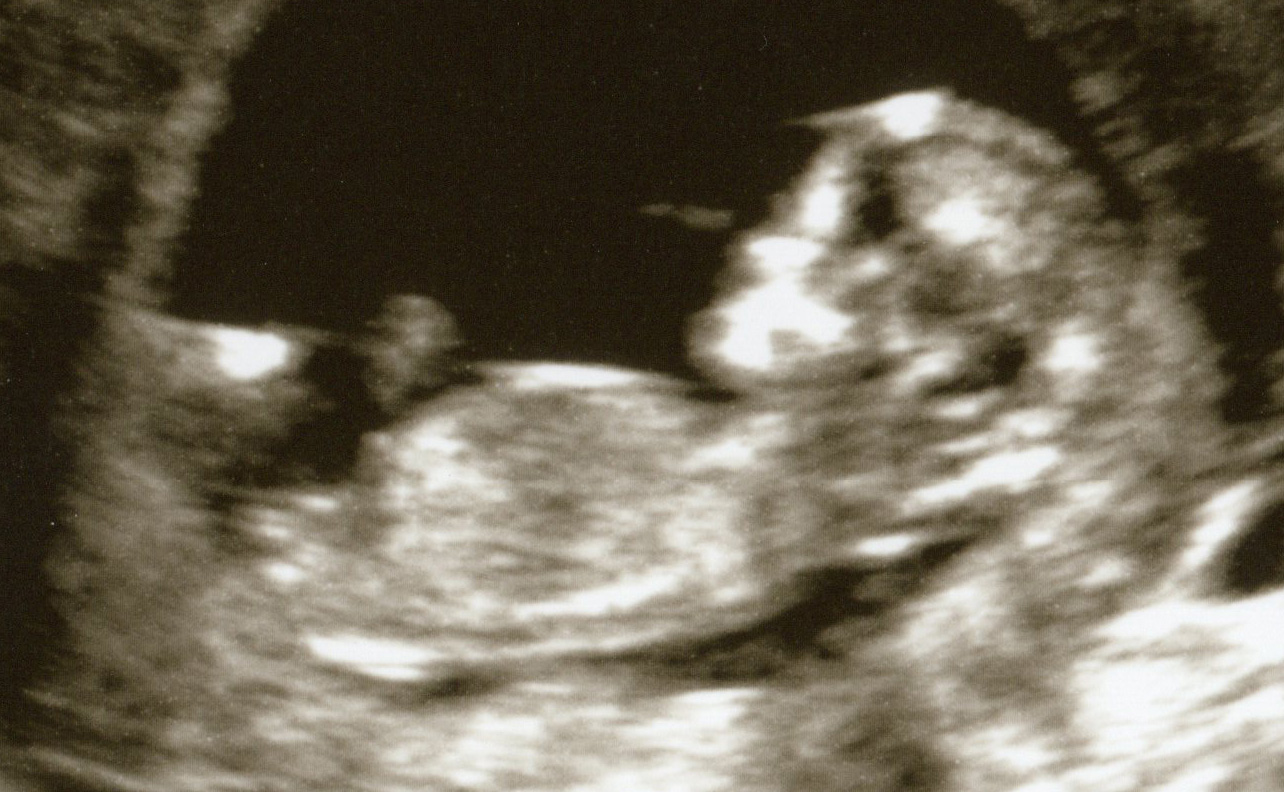

Potty shot at 13w3d:

Attachment 3214